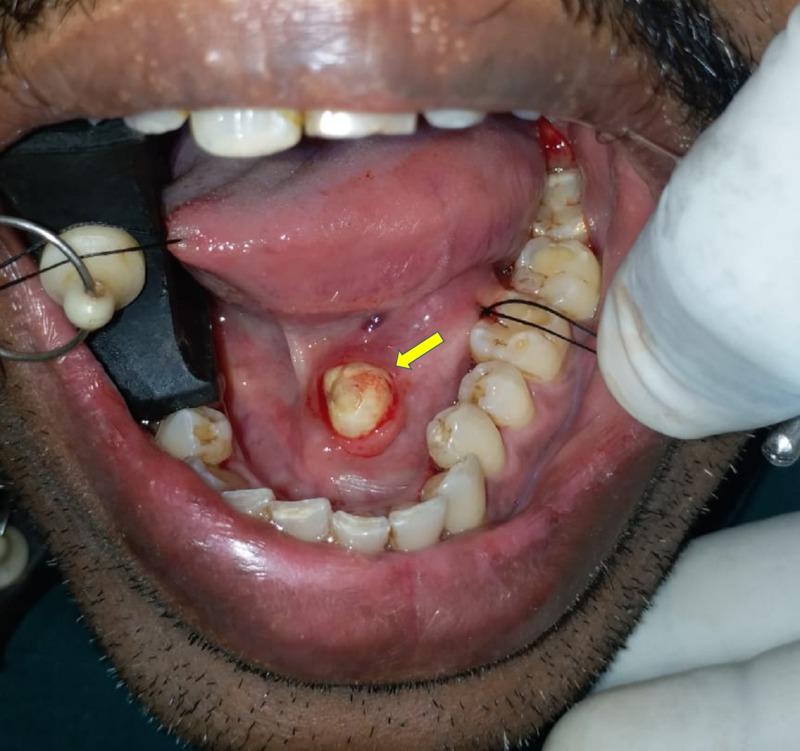

Sialolithiasis is the formation of calcific concretions within the parenchyma or ductal system of the major or minor salivary glands, but it most commonly affects the submandibular salivary gland. Sialolithiasis usually occurs in adults aged 30 to 60 years and causes pathognomonic pain during meals. The treatment of sialolithiasis depends on the size and location of the calculi. We present two cases of sialolithiasis of the submandibular gland managed via the intraoral and extraoral approaches, depending on the position of the calculi.